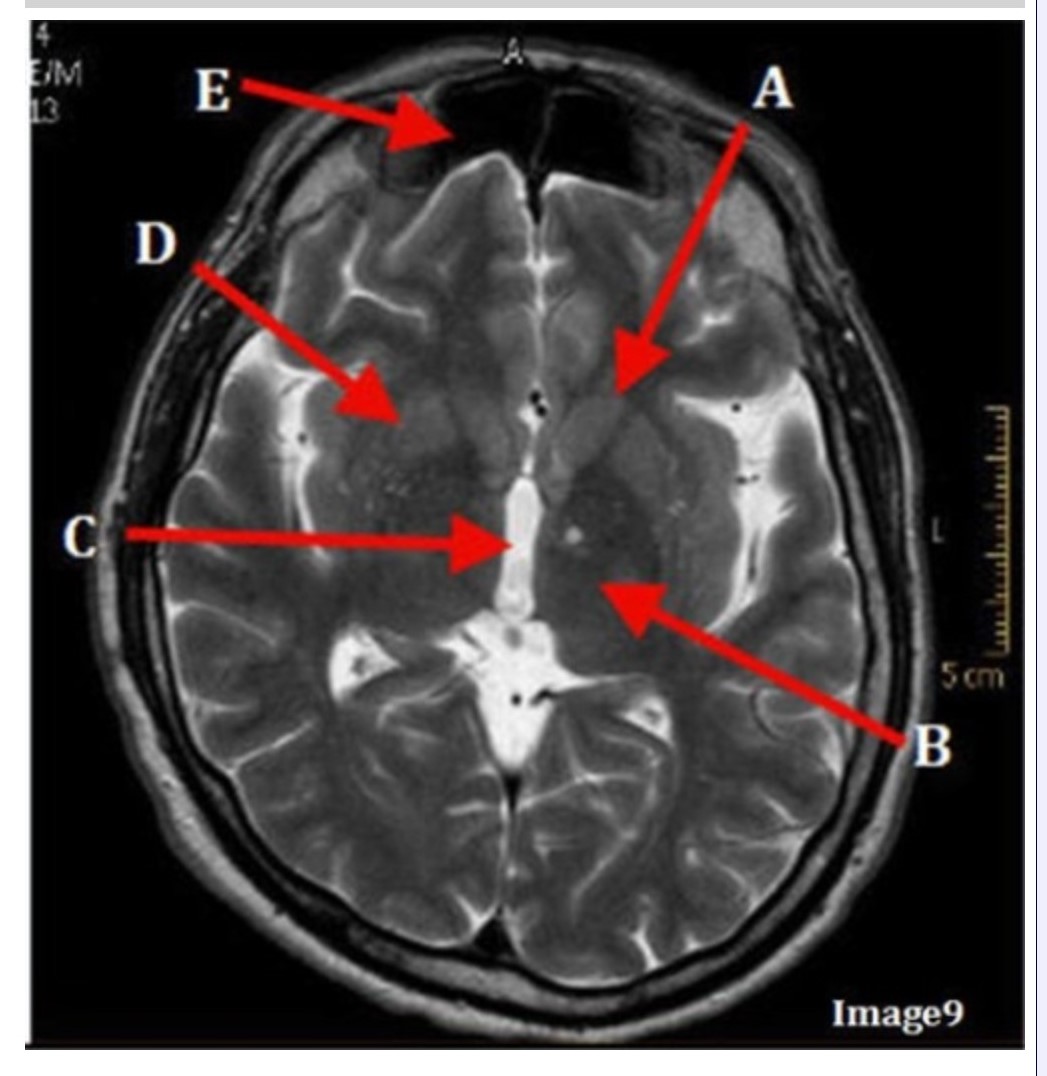

Letter C in Image 9 is pointing to:

A. Third ventricle

B. Thalamus

C. Lentiform nucleus

D. Caudate nucleus

Letter B in Image 9 is pointing to:

A. Third ventricle

B. Thalamus

C. Lentiform nucleus

D. Caudate nucleus

Letter D in Image 9 is pointing to:

A. Third ventricle

B. Thalamus

C. Lentiform nucleus

D. Caudate nucleus

Letter E in Image 9 is pointing to:

A. Maxillary sinus

B. Sphenoid sinus

C. Frontal sinus

D. Ethmoid sinus

Letter A in Image 9 is pointing to:

A. Third ventricle

B. Thalamus

C. Lentiform nucleus

D. Caudate nucleus

Image 9 is an example of a _____ weighted sequence acquired in the _______ scan plane.

A. T1; Axial

B. T2 FLAIR; Sagittal

C. T2; Axial

D. T2; Coronal